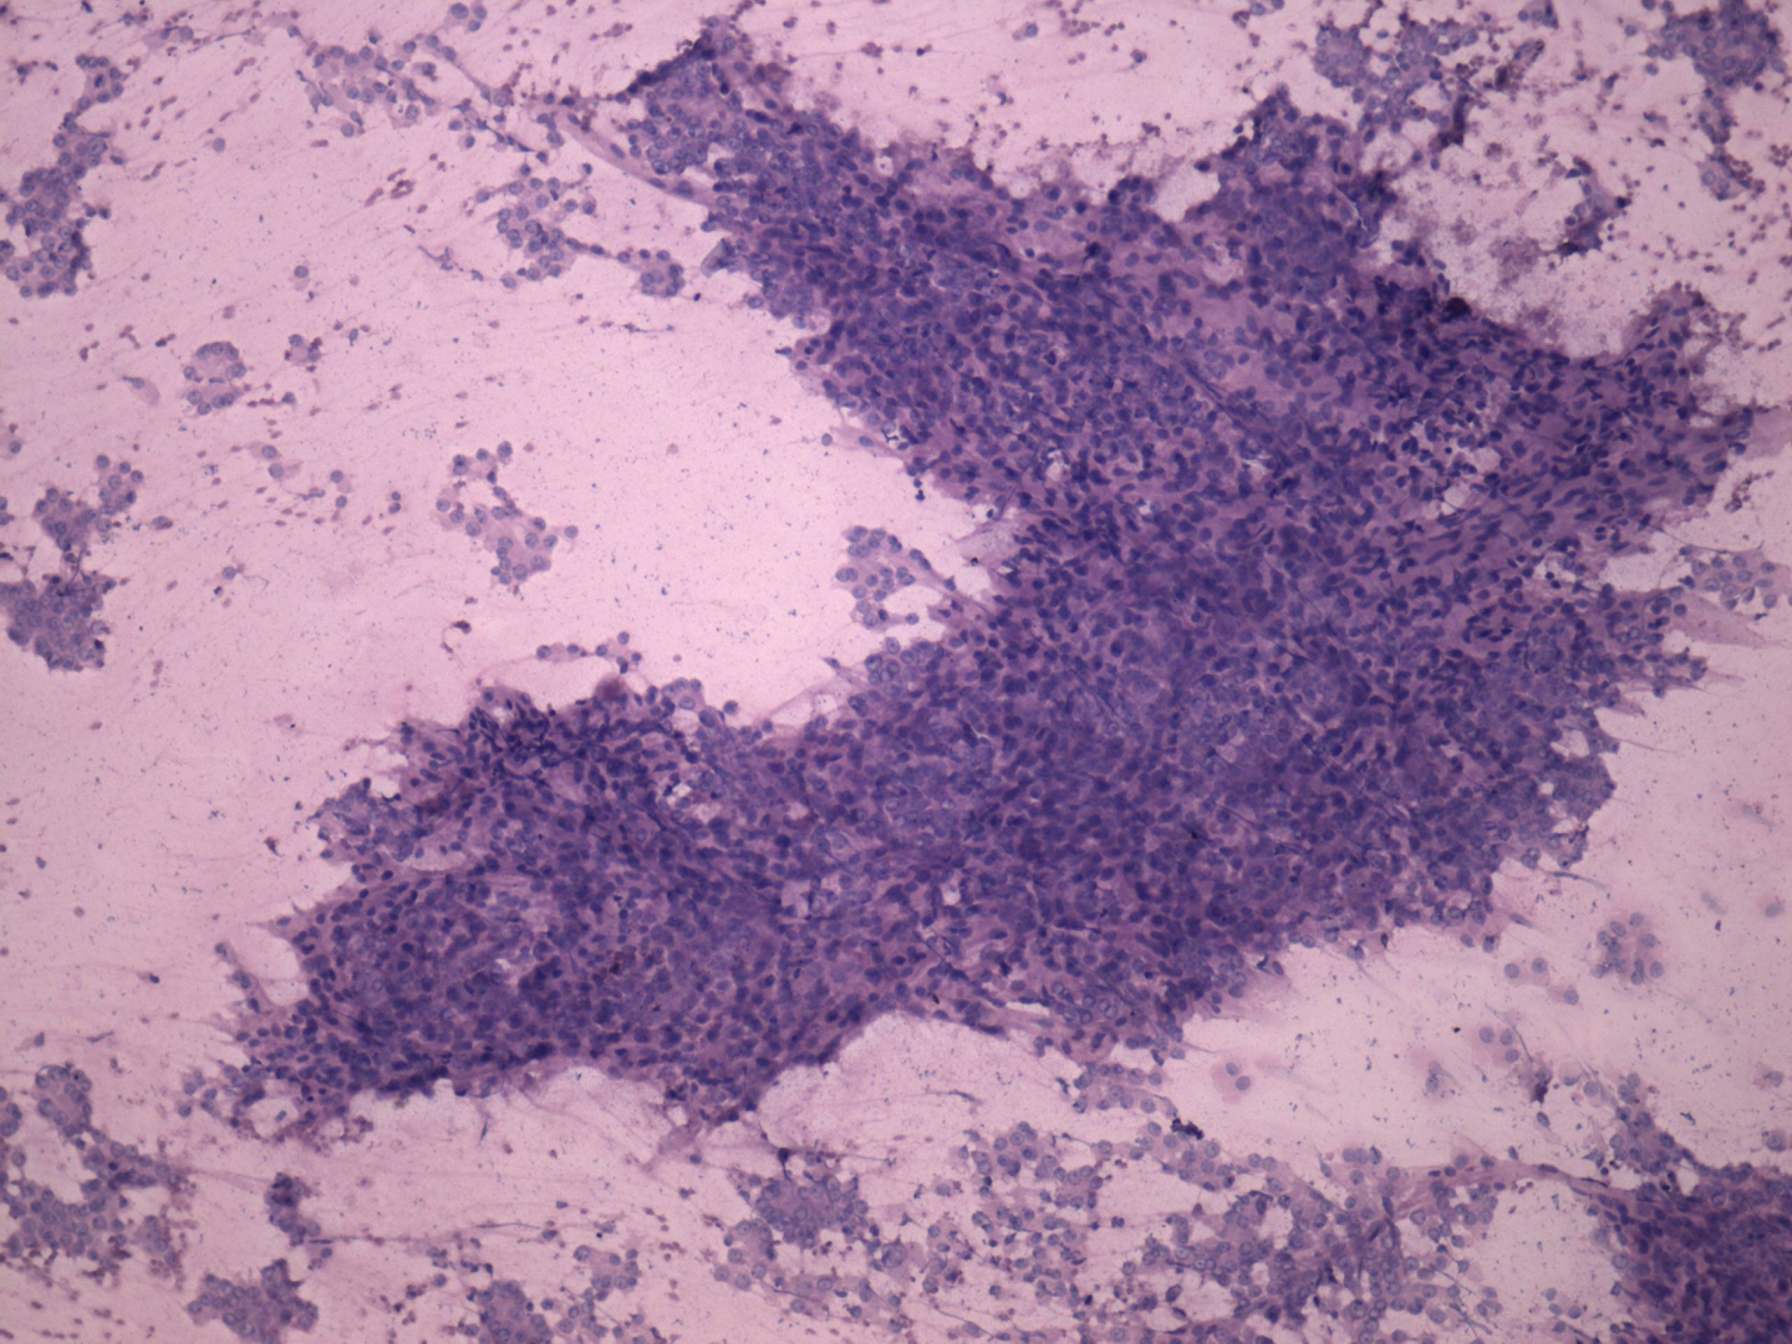

Poorly differentiated inzular carcinoma (cytologic picture 3)

Pap-smear, 200x. Microfollicular proliferation. The cells have abundant cytoplasm and are of even size.